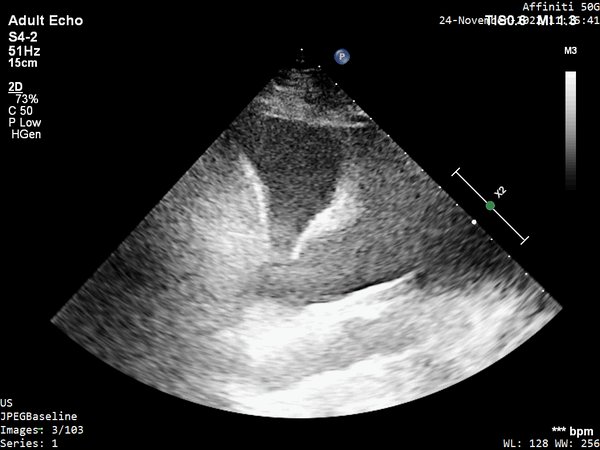

You are asked to do POCUS on a 72 y/o lady with increasing norepinephrine requirements (0.4 mcg/kg/min) and lactate second day post total pancreatectomy and splenectomy for ca.

3/ And more POCUS clips for you.

A4C

5/ PLAX

22/ I went back to see her a week later because I was really curious to see her in a 'lower flow state'. I wanted to check the aortic valve (is there stenosis?) and also the mitral (some hidden nuggets there).

Intraventricular obstruction almost disappeared...